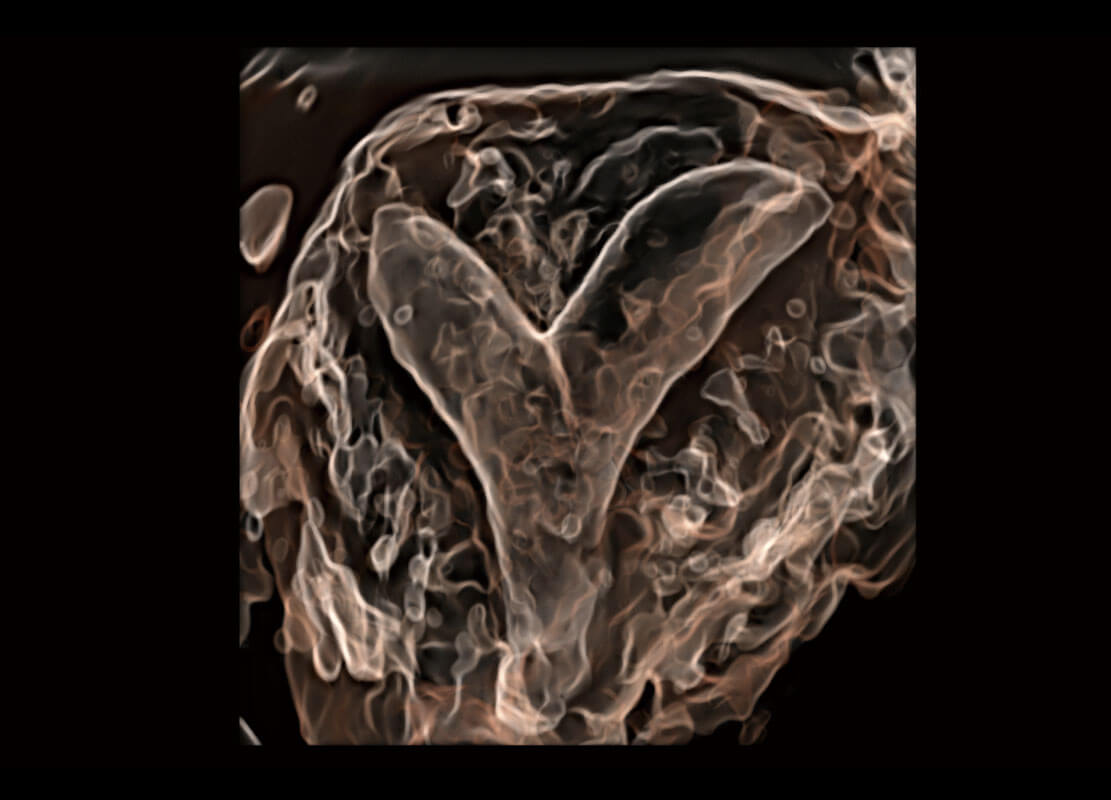

P60搭载一系列胎儿心脏成像技术,实现精细的胎儿心脏评估。

胎心容积成像